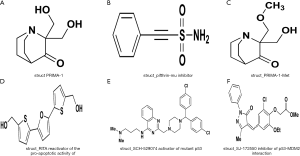

CTRP analysis

Finally, we used CTRP to explore the potential drugs and small molecules that target TP53 signaling pathway genes. The results showed that six small molecules, including PRIMA-1, pifithrin-mu, PRIMA-1-Met, RITA, SJ-172550, and SCH-529074, target the TP53 signaling pathway (Figure 16). Among the small molecules, RITA and SCH-529074 were activators of TP53, while pifithrin-mu and SCH-529074 were inhibitors.

The ultimate goal of many studies is to find more effective treatment protocols to lengthen the lifespan of, and to even cure, patients. Therefore, we used the HPA dataset to explore the location of TP53 expression. The results showed that TP53 expression is localized in the nucleus and could be inhibited by siRNA. Recent studies have explored whether siRNAs can be used to treat cancer. Singh et al. showed that siRNA could be used to deliver anticancer drugs and to inhibit genes at the post-transcriptional level (54). The effectiveness of anticancer drugs can be considerably influenced by their absorption, distribution, metabolism, and excretion. TP53 expressed in the nucleus can lead to the development of resistance to some anticancer drugs (55). TP53 is the most mutated gene in multiple cancers and the reactivation of its inactive mutated form represents a possible target for antitumor therapy. Further, we used the CRTP dataset to explore the potential target drugs and small molecules of the TP53 signaling pathway. The results showed that PRIMA-1, pifithrin-mu, PRIMA-1-Met, RITA, SJ-172550, and SCH-529074. PRIMA-1, and Prima-1-Met were activators of TP53. Activation of TP53 can induce cancer cell apoptosis (56). Pifithrin-mu was shown to inhibit heat shock protein 70 (HSP70) and could be combined with other chemotherapy drugs to improve their efficacy (57). Pifithrin-mu also served as the anticancer molecule of NSCLC (58). RITA is a small molecule that blocks TP53-MDM2 interaction, thereby reactivating TP53 in tumors to induce tumor cell apoptosis. RITA combined with 3-methyladenine (3-MA) can be used to treat chemoresistance in head and neck cancer by inhibiting the autophagy and antioxidant systems (59). We used the cBioPortal dataset to explore the TP53 signaling pathway. The results showed that TP53 also interacted with MDM4. SJ-172550 is an inhibitor of the interaction of TP53 and MDM4 (60), while SCH-529074 can reactivate mutated TP53 to suppress NSCLC cell growth (61).